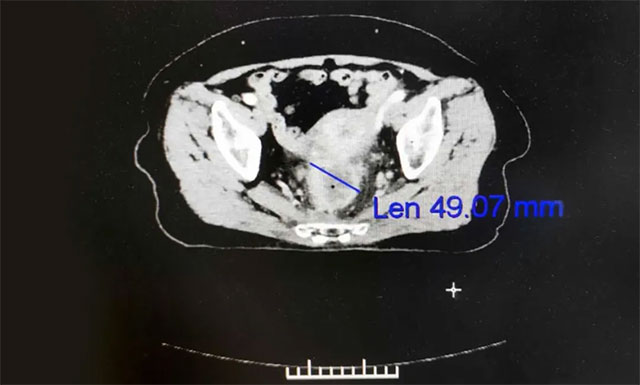

▲ 患者直肠癌再次复发,病情严重

经过复查,发现刘女士直肠局部肠壁不规则增厚,考虑仍有肿瘤活性,伴直肠周围、左髂血管旁及腹膜后大血管多发淋巴结转移,腹部造瘘术后改变,右半结肠炎性改变。之后,为求进一步放射治疗,刘女士在家人的陪伴下于7月6日慕名就诊于上海蓝十字脑科医院。

▲ 放疗后患者病灶缩小,病症逐渐缓解